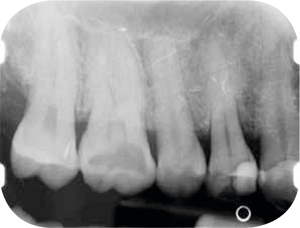

Afb. 11-12

Bitewings. Met de initiële fase is al een aanvang gemaakt.

Röntgenonderzoek

Röntgenologisch onderzoek laat meerdere problemen zien. Onder andere een forse zwarting apicaal van element 12 met het beeld passend bij periapicale problematiek en een verleden van apicale chirurgie (afbeelding 8-12 ).